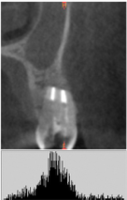

Плотность «CrossBone»® выше плотности костной ткани.

Соотношение плотности зоны дефекта и реперной области (HUд/HUр) на первый день было равно 1,2±0,11.

Высокая плотность «CrossBone»® обусловлена наличием в его составе только неорганических компонентов (рис. 2).

Рис. 2. Гистограмма распределения плотности на дентальной компьютерной томографии фронтального отдела нижней челюсти пациента М. непосредственно после операции РВК зуба 4.1 с заполнением костной полости материалом «CrossBone»®.